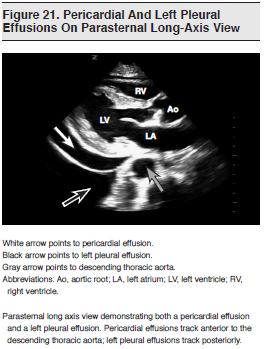

Pericardial fluid typically appears as an anechoic space between the epicardium and the pericardium. (See Figure 21.) Ultrasound is an ideal modality to detect the presence of pericardial fluid and its impact on right heart filling.177,189,190 Although cardiac tamponade is largely a clinical diagnosis, emergency echocardiography may demonstrate findings consistent with impending tamponade prior to the development of physical examination findings and hemodynamic compromise.191-193 The amount of fluid required to impair filling and cause circulatory failure depends on the rate of accumulation. Pericardial effusions may be graded as small (less than 10 mm), moderate (10-15 mm), or large (greater than 15 mm).193-196

Numerous studies have demonstrated that emergency physician–performed emergency echocardiography has sensitivities approaching 100% for the detection of pericardial effusions.184,197,198 When compared with the expert over-read of images, emergency physician–performed emergency echocardiography for effusion has a sensitivity of 96% to 100%, a specificity of 98% to 100%, a positive predictive value of 93% to 100%, and a negative predictive value of 99% to 100%.1 The echocardiographic findings consistent with cardiac tamponade include the following: right ventricular (RV) free wall inversion during ventricular diastole (the hallmark finding), right atrial inversion during ventricular systole (more common and one of the earliest findings), increased respiratory variation of mitral or aortic inflow velocities (inspiratory decrease greater than 25%), and a dilated inferior vena cava with decreased inspiratory collapse.196